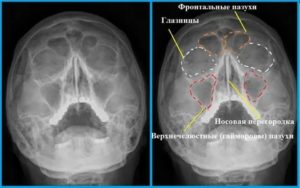

Рентген пазух носа здорового человека выглядит следующим образом:

- Гайморовы пазухи представлены в виде треугольных полостей по бокам.

- Носовая полость разделена на симметричные части носовой перегородкой.

- Носовые ходы представлены в виде белых полос, проходящих по обе стороны разделенной области.

- Ячейки решетчатой пазухи должны быть четко видны (она расположена под глазницами).

- Пазухи должны обладать ровными и четкими краями.

Рентген пазух носа здорового человека

В норме здоровая носовая полость на рентгеновском снимке имеет четкие контуры. Рентген показывает небольшую величину и среднюю толщину стенок решетчатого лабиринта придаточных пазух.

Сами придаточные пазухи выглядят как темные, полуовальной формы, образования по обе стороны носа, а их воздушность совпадает с воздушностью в области орбит (т. е.

прослеживается идентичность оттенков глазниц и синуса).

В норме рентгена пазухи носа чистые, контуры ровные, светлого содержимого нет

У здорового человека околоносовые синусы выглядят как темные образования, имеющие полуовальную форму. Они располагаются по обе стороны срединной линии лица. Для выявления изменений (затемнений) интенсивность окрашивания на снимке сравнивают с цветом орбит глаз. В норме он отличаться не должен.

Эта процедура дает широкие возможности для постановки и подтверждения различных заболеваний околоносовых синусов. Полученные снимки (рентгенограммы) помогают врачам визуализировать и рассмотреть такие анатомические части: лобные, гайморовые (верхнечелюстные) пазухи, решетчатый лабиринт, глазницы и кости лицевого черепа.